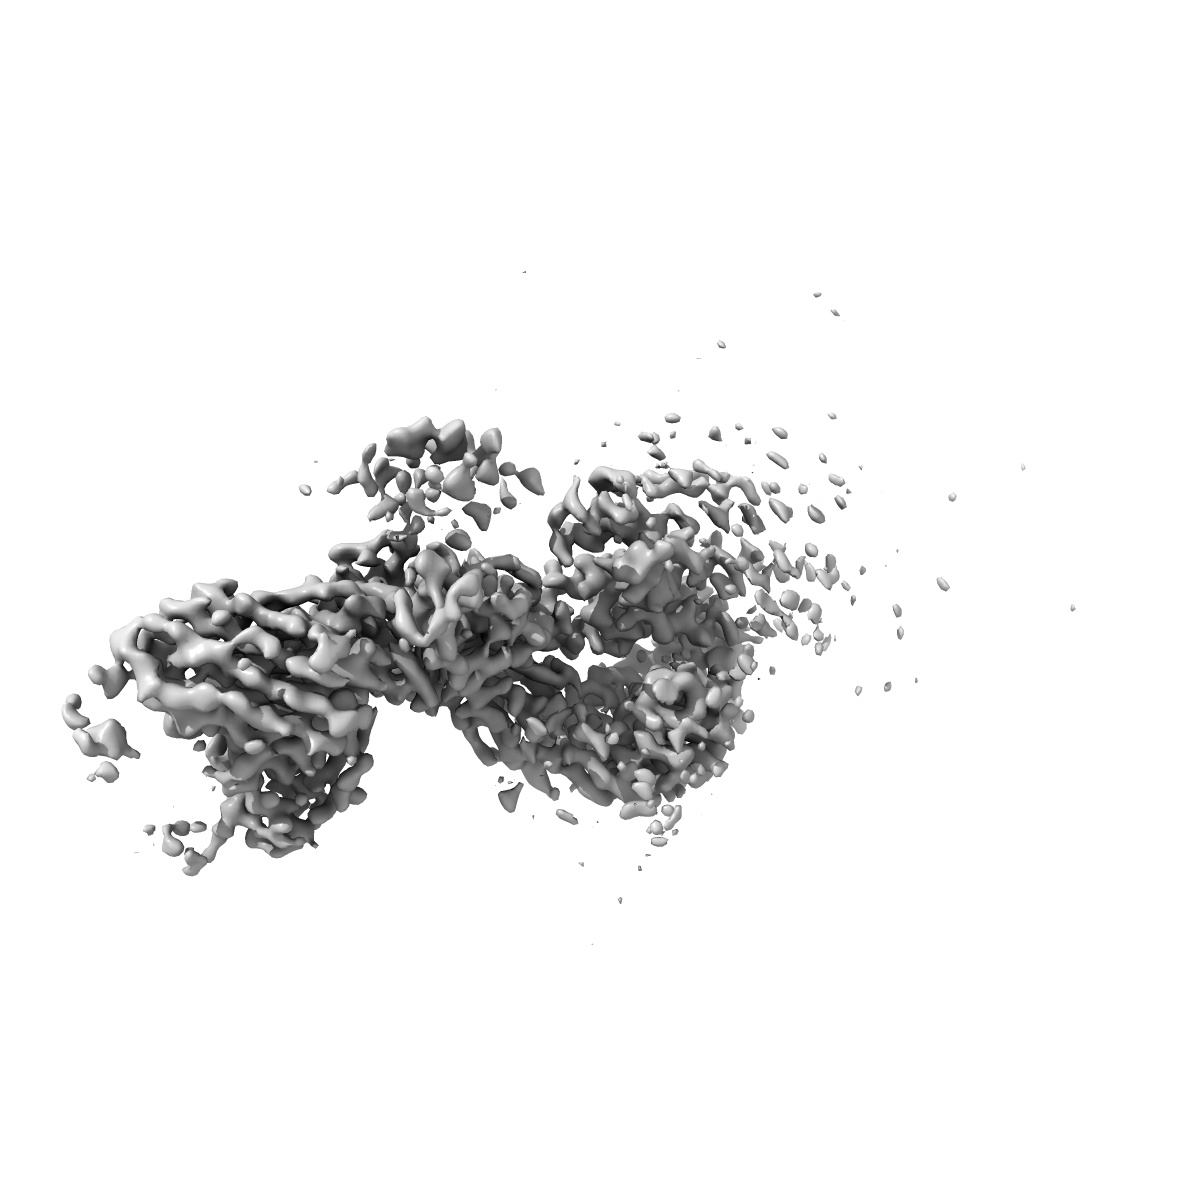

EMD-19002

XBB-4 Fab in complex with SARS-CoV-2 BA.2.12.1 Spike Glycoprotein

Single-particle3.41 Å

Sample: XBB-4 Fab in complex with SARS-COV-2 BA.2.12.1 Spike Glycoprotein

Fitted models: 8r8k